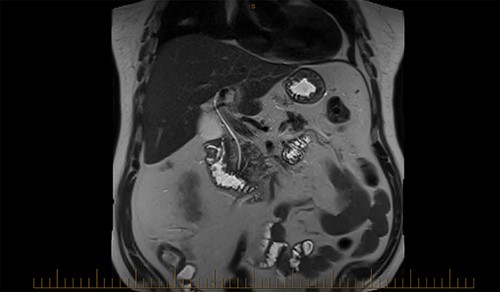

A magnetic cholangiopancreatography (MRCP) was performed to exclude a cholecystoduodenal fistula. A filling defect within the duodenum was identified on the scan; however, there was no evidence of a fistula (Fig. 6).